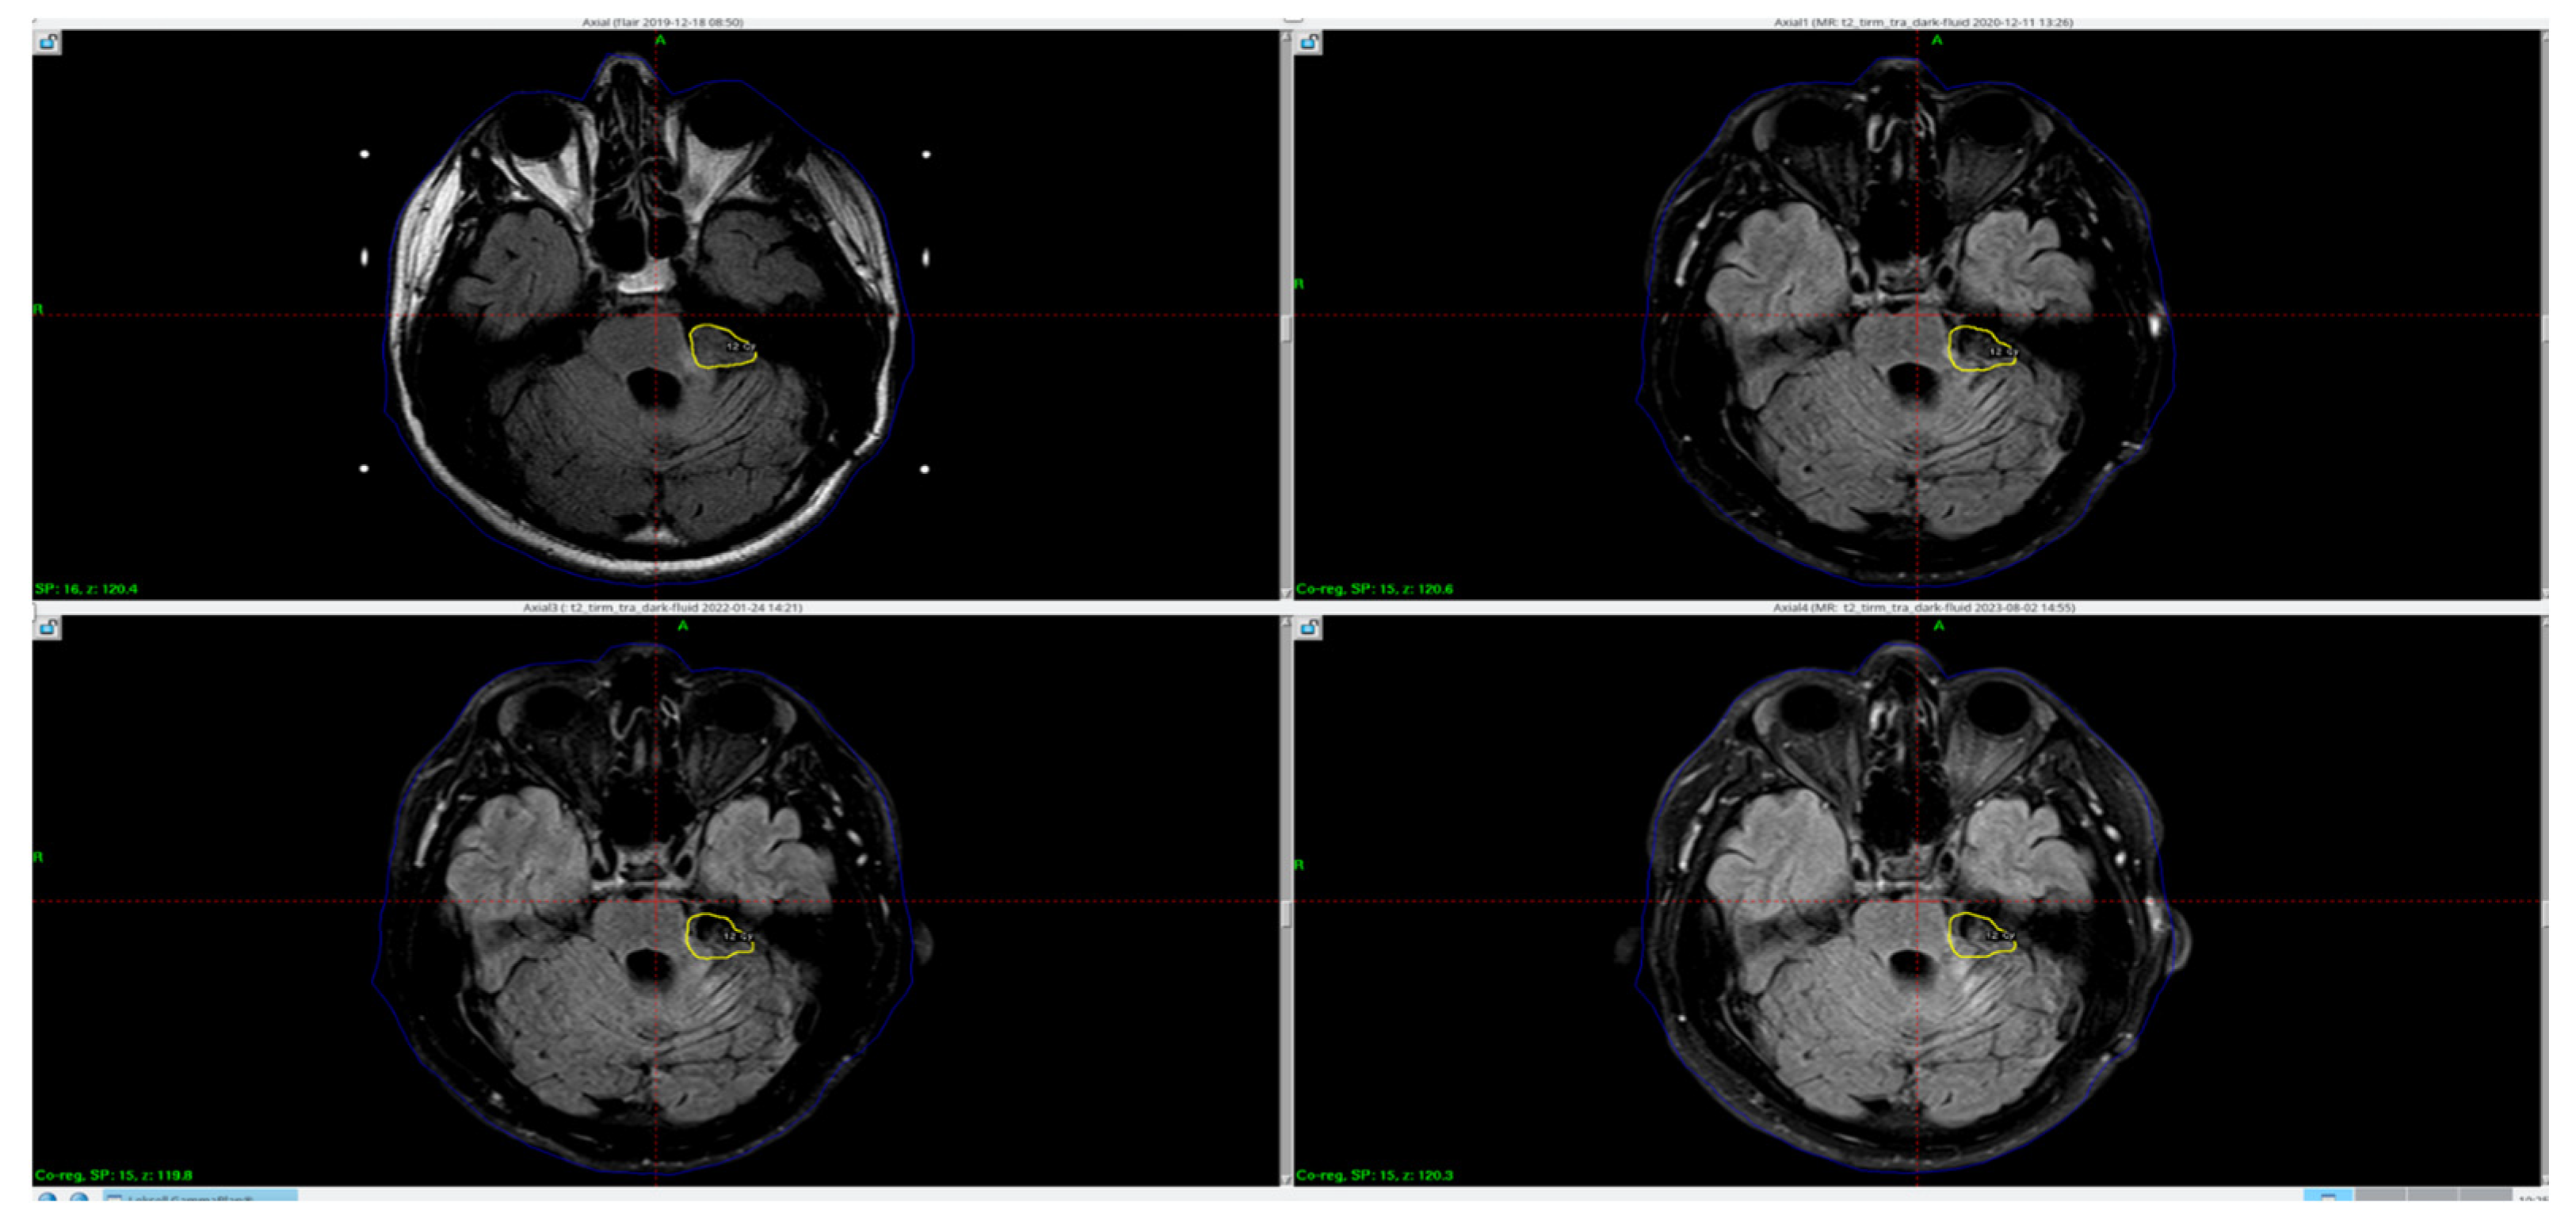

The MRI examination performed after Gamma Knife therapy showed also an additional linear lesion of increased signal intensity. The FLAIR sequence in the vicinity of the walls of the ventricular system, and a band of increased signal in the posterior part of the corpus callosum with moderate thinning at this height are shown in Figure 2.

Figure 2. Hyperintense signal within the splenium of corpus callosum visible in the MRI FLAIR sequence in subsequent MR examinations—from the left: 12.2019, 06.2020, 12.2020, 01.2022 (blue arrows).